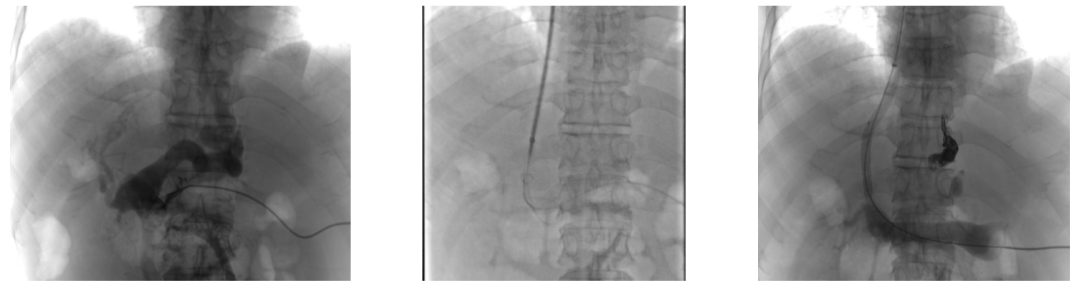

背景与目的

经脾门静脉再通辅助下经颈静脉肝内门体分流术(Trans-splenic PVR-TIPS)可能是治疗门静脉闭塞患者的一种有效手段。然而,由于其技术复杂,目前的研究多为病例报告或小样本研究,其安全性和有效性尚需进一步验证。为此,我们开展了一项多中心回顾性研究,以评估Trans-splenic PVR-TIPS的安全性与有效性。

本研究为多中心回顾性研究,纳入2018年6月至2023年6月期间接受Trans-splenic PVR-TIPS治疗的67例患者。主要评估指标包括手术成功率、并发症发生率以及远期门静脉再通率(门静脉主干残余腔道面积≥50%者的比例)。根据辅助技术的不同,将患者分为球囊辅助组(balloon-assisted Trans-splenic PVR-TIPS)与圈套辅助组(snare-assisted Trans-splenic PVR-TIPS),比较两组的辐射暴露情况与并发症发生率,以评估哪种引导技术更为优化。

本研究共纳入67例患者,手术成功率为95.5%(64例)。除1例因支架内细菌定植引发脓毒症外,未观察到其他严重的术相关并发症。中位随访时间为37个月,1年门静脉通畅率为90.6%,全程随访期间支架通畅率为81.3%。在门静脉再闭塞的患者中,75%发生于术后前两年内。与球囊辅助组相比,圈套器辅助组的总手术时间(155.2±32.8分钟vs. 134.0±34.5分钟,P= 0.015)及透视时间(68.9±19.3分钟vs. 59.4±17.95分钟,P=0.045)更短,但脾脏相关不良事件发生率差异无统计学意义(9.7%vs. 3.0%,P=0.347)。

经脾PVR-TIPS是一种在治疗门静脉闭塞中具有良好安全性与有效性的手术方式,具有较高的技术成功率、低术后不良事件发生率及较理想的远期门静脉通畅率。此外,圈套器辅助技术的应用有望在降低术中辐射暴露的同时,进一步减少手术相关并发症。